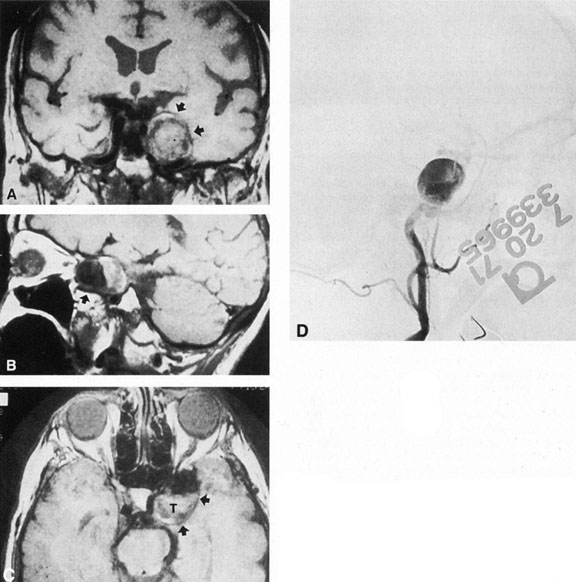

Fig. 3. Magnetic resonance images of intracavernous aneurysm in a 72-year-old woman with left retrobulbar pain and sixth-nerve palsy. A: Coronal section (TR, 800 ms; TE, 30 ms). B: Parasagittal section (TR, 1000 ms; TE, 20 ms). C: Axial section (TR, 800 ms; TE, 30 ms). Note partial occlusion by thrombus (T). D: In a similar patient, carotid arteriogram (subtracted, lateral view) demonstrates a large intracavernous aneurysm.

Intracavernous aneurysms are suspected by the clinical presentation of a chronic cavernous sinus syndrome and are diagnosed by enhanced computed tomography (CT), magnetic resonance imaging (MRI), and arteriography (see Fig. 3). Because of the location and configuration within the cavernous sinus, direct surgical approaches to cavernous carotid aneurysms are hazardous. In recent years intravascular occlusion of the internal carotid by detachable balloon has evolved as a safe and successful procedure, often with relief of pain and improvement in ophthalmoplegia.10 Unfortunately, these balloons are commercially unavailable at the time of this writing.